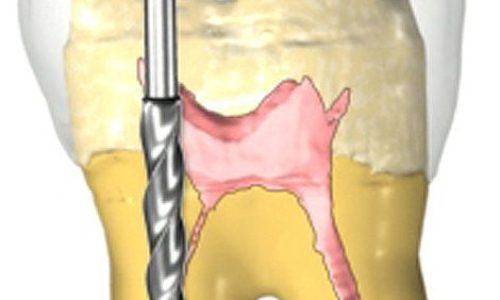

Implantología

Especialidad que permite sustituir piezas dentales perdidas mediante la colocación quirúrgica de un implante en el hueso maxilar o mandibular, devolviendo la capacidad masticatoria, fonética y estética al paciente. Devolviendo la capacidad masticatoria, fonética y estética al paciente.